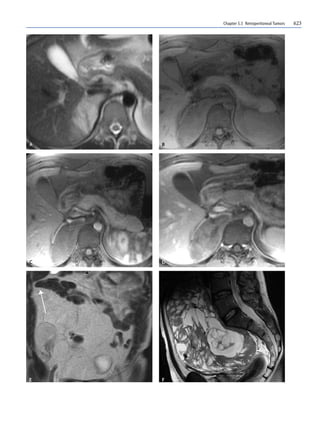

Fig. 2A–D. Densitometric characteristics of retroperitoneal tu-

mors.CT examinations before (A) and after (B–D) CM administra-

tion. A Lipoma. Well-circumscribed lesion with homogeneous fat

density. B Liposarcoma. Voluminous lesion, displacing the intesti-

nal loops toward the left with fat density and within which fibrous

septa are visible. C Leiomyosarcoma. Voluminous lesion originat-

ing from the wall of the vena cava and within which necrotic areas

can be seen. D Ganglioneurofibroma. Solid lesion with clear mar-

gins and low density (myxoid stroma)

Fig. 3A–F. MR aspects of retroperitoneal tumors. A–D Ganglioneu-

roma. In the dynamic contrast-enhanced study (A–C), the lesion

shows delayed enhancement.In the T2-weighted axial scan (D),the

lesion has a whorled appearance due to the abundance of collagen

fibers. E Liposarcoma. In the turbo spin-echo (TSE) T2-weighted

coronal scan, the lesion shows a signal hyperintensity due to the

fatty content. The hollow organs appear prevalently displaced up-

ward.An embedded sign can be seen in the right hypochondrium

(arrow). F Synovial sarcoma. In the T2-weighted sagittal scan, the

lesion has a heterogeneous pattern with areas of high signal inten-

sity (necrosis) and low signal intensity (solid tissue): bowl of fruit

sign. The lesion appears well defined

The myxoid stroma is hyperintense in T2- and hypo-

intense in T1-weighted images. After contrast medium

(CM) administration,the enhancement is slower.This is

common with ganglioneuroma (Fig. 3A–D), schwanno-

ma, neurofibroma, myxoid liposarcoma, malignant fi-

brohistiocytoma, ganglioneuroblastoma and malignant

tumor of the peripheral nerve sheaths.

The collagen fibers are hypointense in T1- and T2-

weighted images.After CM, the dense areas of the colla-

gen fibers enhance more slowly. Lesions that contain

collagen fiber include neurofibroma, ganglioneuroma

(Fig. 3A–D), leiomyosarcoma, malignant fibrohistiocy-

toma, malignant tumor of the peripheral nerve sheaths,

fibrosarcoma and retroperitoneal fibrosis.

Fat is rather hyperintense in T1,moderately hyperin-

tense in T2 (fast or turbo spin-echo sequences) and hy-

pointense in fat-suppressed images. Lesions made up of

or often containing fat are lipoma, myelolipoma, an-

giomyolipoma and well-differentiated liposarcoma

(Fig. 3E).

쐌 Target sign: central area with a low or intermediate

signal surrounded by a hyperintense ring in T2. His-

tologically it corresponds to fibrous tissue centrally

and myxoid tissue around the edge. It is frequently

seen in neurofibromas and schwannomas.

쐌 Bowl of fruit sign: low intensity mosaic,intermediate

and high signal in T2-weighted images due to a com-

bination of solid components, cystic degeneration,

hemorrhage, myxoid stroma and fibrous tissue. This

is often seen in malignant fibrohistiocytoma,synovi-

al sarcoma (Fig. 3F) and Ewing’s sarcoma.

쐌 Whorled appearance: a linear or curvilinear struc-

ture appearing hypointense in T2.It corresponds to a

band of Schwann cells and collagen fiber in the mass.

It is commonly seen in ganglioneuroma (Fig.3d) and

neurofibroma.